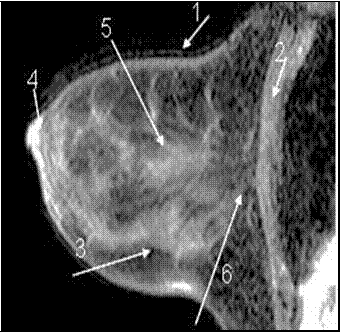

МР-маммограммы женщин репродуктивного возраста характеризовалась неоднородностью МР-структуры. В МЖ на фоне железистых, протоковых и соединительнотканных структур (связок Купера), которые отличались низкой интенсивностью МР-сигнала, также определялись участки жировой ткани с высокой интенсивностью сигнала (рис. 23).

Рисунок 23 — МР-маммограмма здоровой МЖ женщины репродуктивного возраста.

1 – кожа, 2 – грудная мышца, 3 – жировая ткань, 4 – сосок, 5 —

железистая ткань, 6 — ретромаммарное пространство. Соотношение железистой и жировой ткани приблизительно одинаковое, дополнительные образования не выявлены.